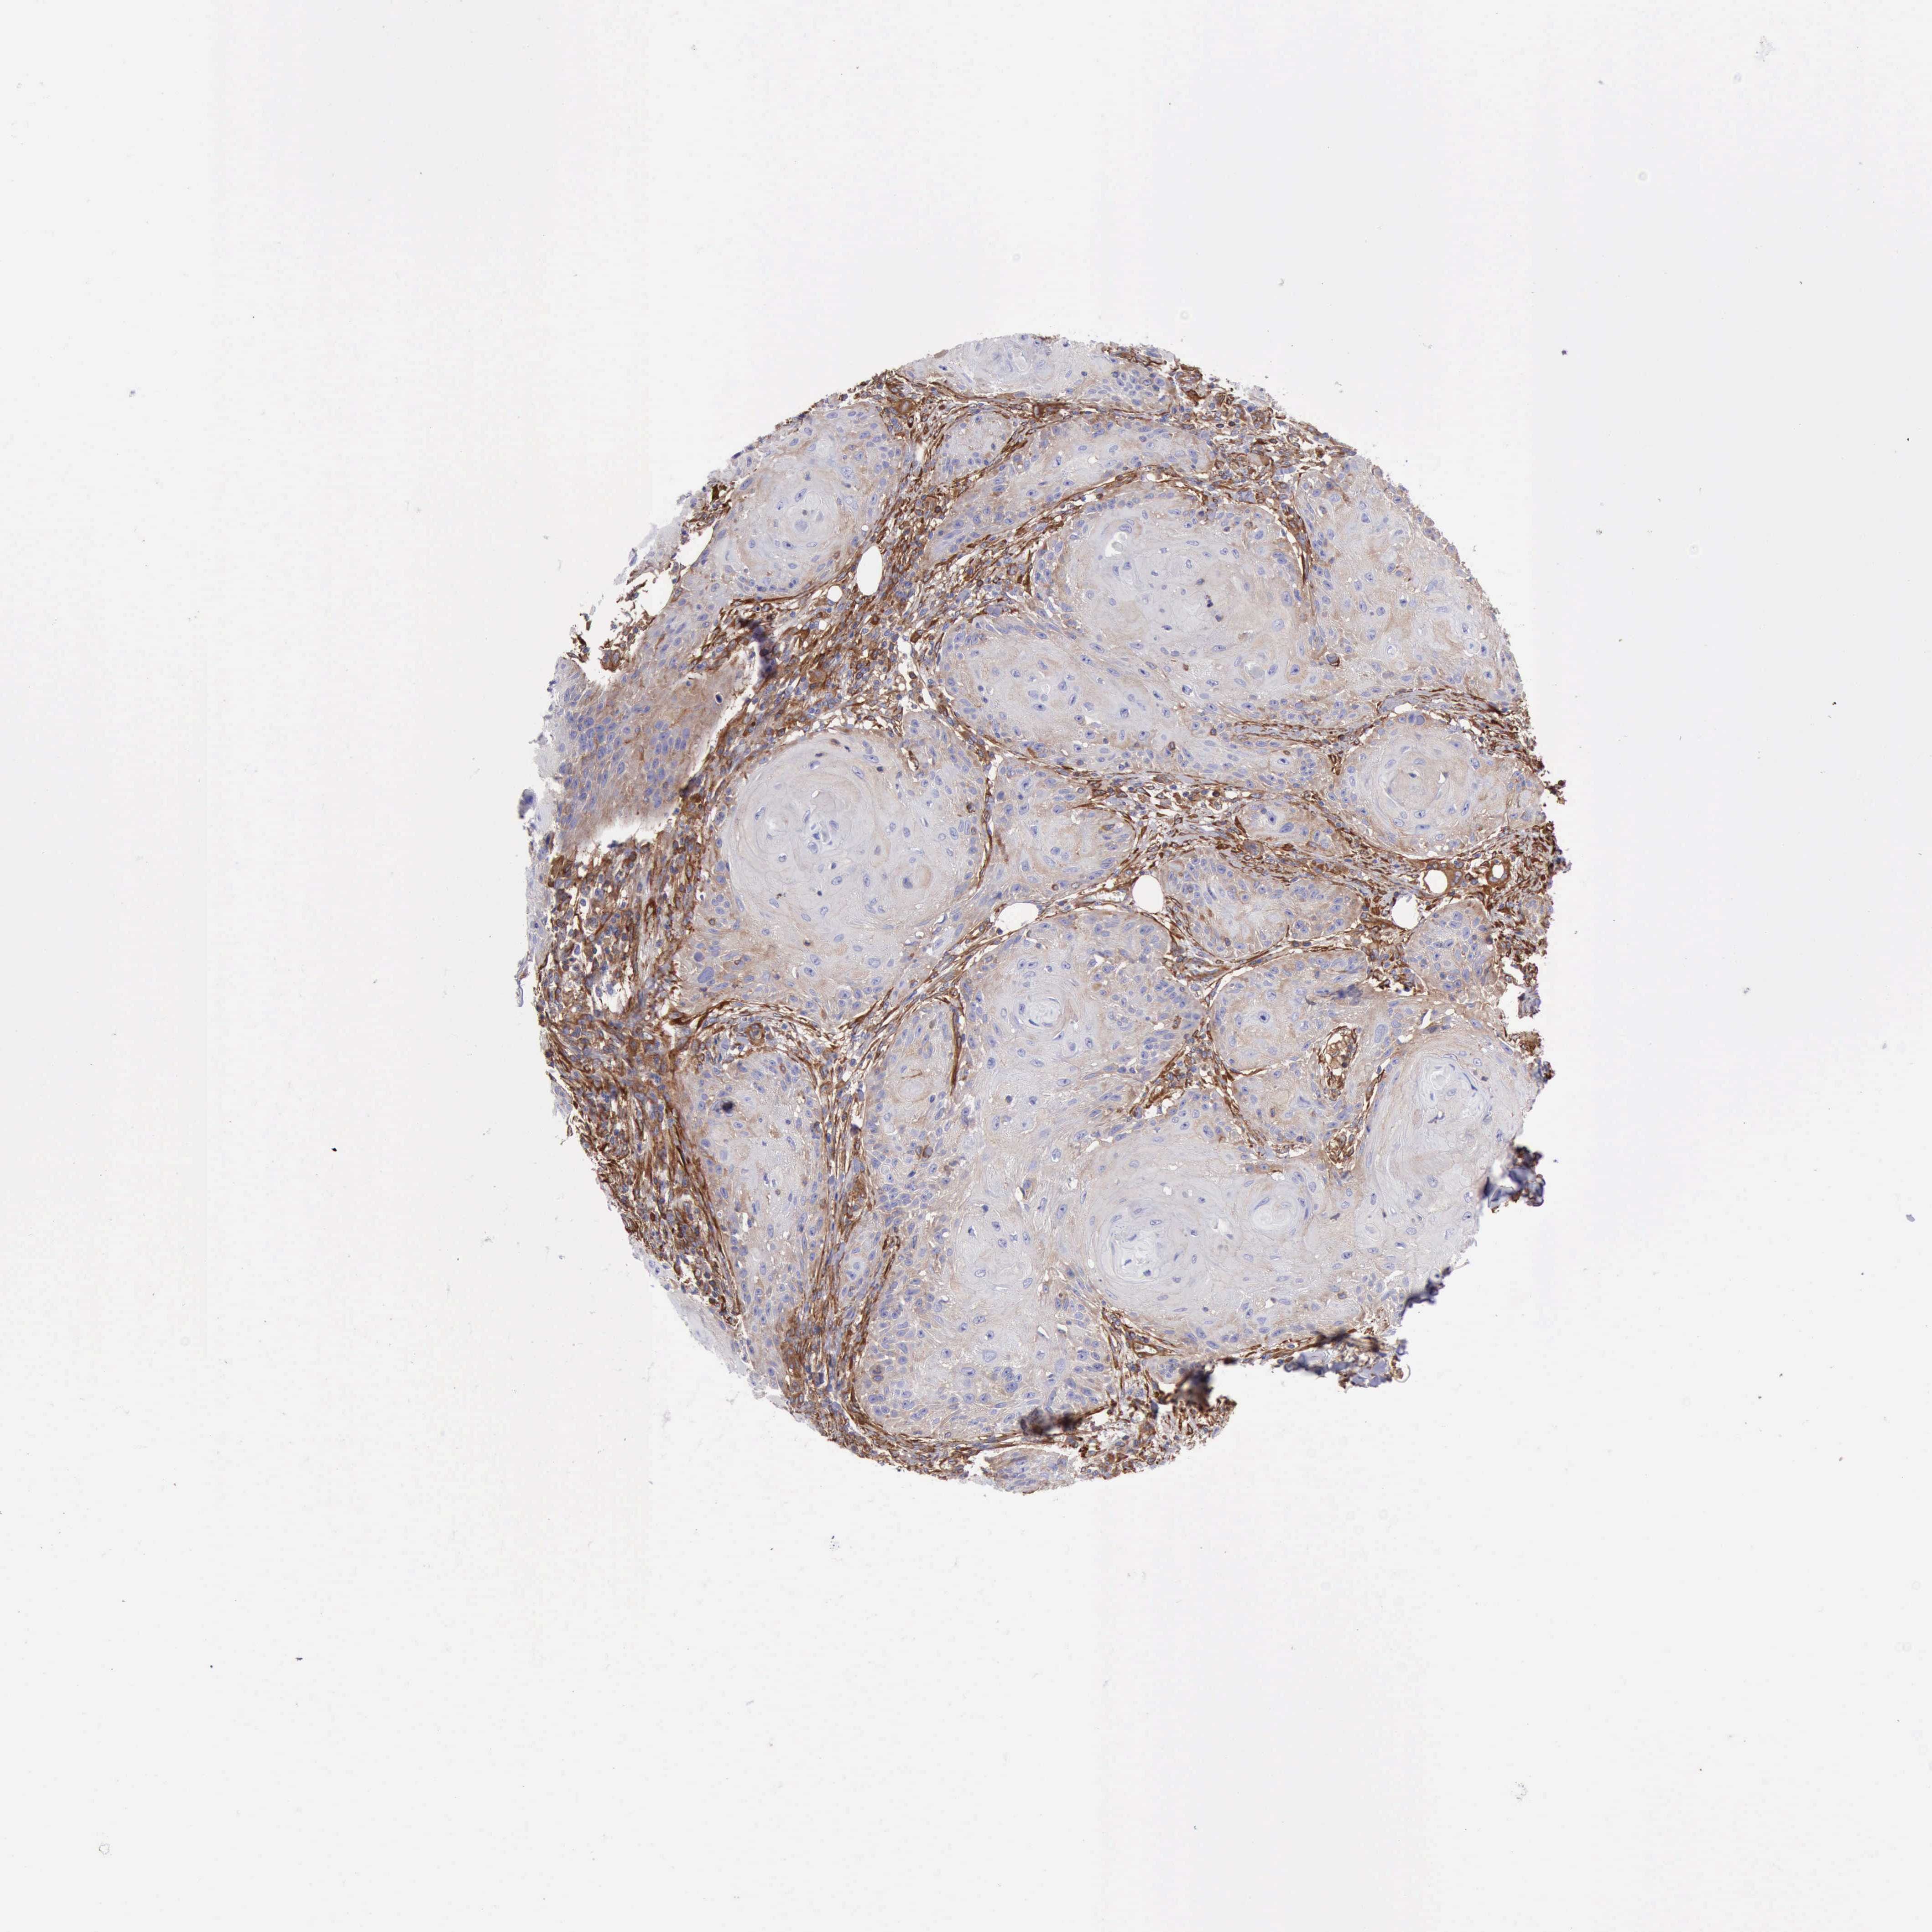

SKIN CANCER - Protein expressioni

A mouse-over function shows sample information and annotation data. Click on an image to view it in a full screen mode. Samples can be filtered based on level of antibody staining by selecting one or several of the following categories: high, medium, low and not detected. The assay and annotation is described here.

Each image is clickable and will lead to virtual microscopy that enables deeper exploration of all samples and also displays staining intensity scores, fraction scores and subcellular localization as well as patient and tissue information for each sample.

Antibody HPA001115

Staining

High

Medium

Low

Not detected

Intensity

Strong

Moderate

Weak

Negative

Quantity

>75%

75%-25%

<25%

None

Location

Nuclear

Cytoplasmic/membranous

Cytoplasmic/membranous,nuclear

Squamous cell carcinoma, NOS

Basal cell carcinoma